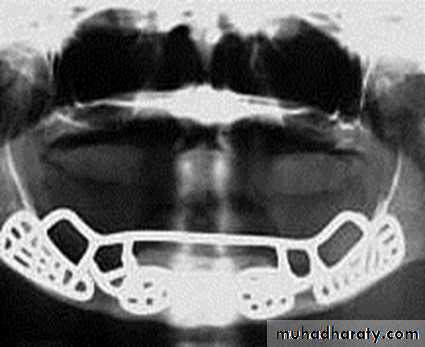

2-Ramus frame implants

Endosteal or Endosseous implantA. Plate-form implant :

• Blade Implants have a long track record, much longer than the Root form Implants. Their name is derived from their flat, blade-like (or plate-like) portion, which is the part that gets embedded into the bone.

These implants are designed for the edentulous lower jaw only and are surgically inserted into the jaw bone in three different areas: the left and right back area of the jaw (the approximate area of the wisdom teeth), and the chin area in the front of the mouth.

It’s indicated in a severely resorbed, edentulous mandible which does not offer enough bone height to accommodate Root form Implants.

It provides a tripodial stabilization of the thin lower jaw and protects it from fracturing.

• Ramus-frame implant

Ramus-frame implant